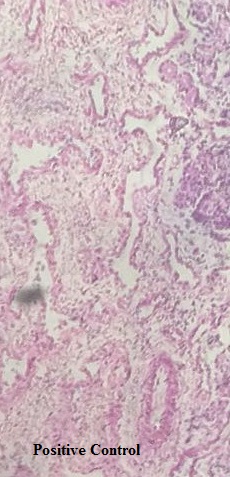

Nasal histopathology was carried out to determine the possible toxic effects of the developed formulation on the surface of the nasal mucosa. Fig. 10 represents five different representative images of sections of nasal mucosa viz., (A) positive control treated, (B) negative control treated, (C) mucosa treated with G5PPID, (D) nasal mucosa treated with G4PPID and (E) nasal mucosa treated with pure donepezil. In the negative control group, nasal mucosa was found to be extensively damaged on the epithelial surface and an internal tissue treated with isopropyl alcohol. The positive control was treated with PBS pH 6.4 and was found to be intact with preserved structure. In the nasal mucosal sections treated with G4PPID and G5PPID, neither structural damage nor cell necrosis was represented and stabilized their biocompatibility. These observations were following the pH value of G4PPID and G5PPID (5.87±0.11) which was within the pH range of human nasal mucosa (5–6.5) indicating its safety for nasal administration [23].

A

B

C

D

E

Fig. 10: Photomicrograph of sections of goat nasal mucosa of (A) positive control group, (B) negative control (C) G5PPID (D) G4PPID and (E) pure donepezil treated (magnification: 400X)